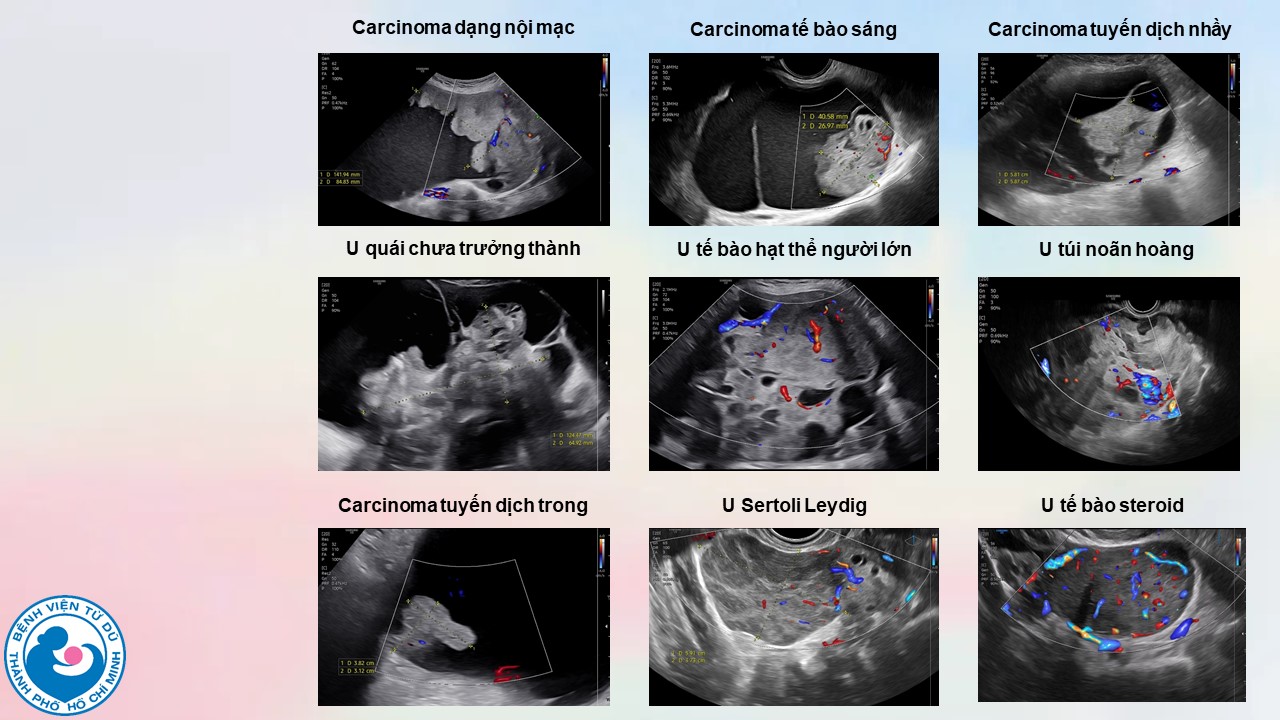

Ứng dụng mô hình ADNEX để chẩn đoán ung thư bường trứng trước phẫu thuật: kinh nghiệm tại bệnh viện Từ Dũ

BS. CKI Vũ Quốc Hùng, Ths. BS. Hà Tố Nguyên - Bệnh viện Từ Dũ